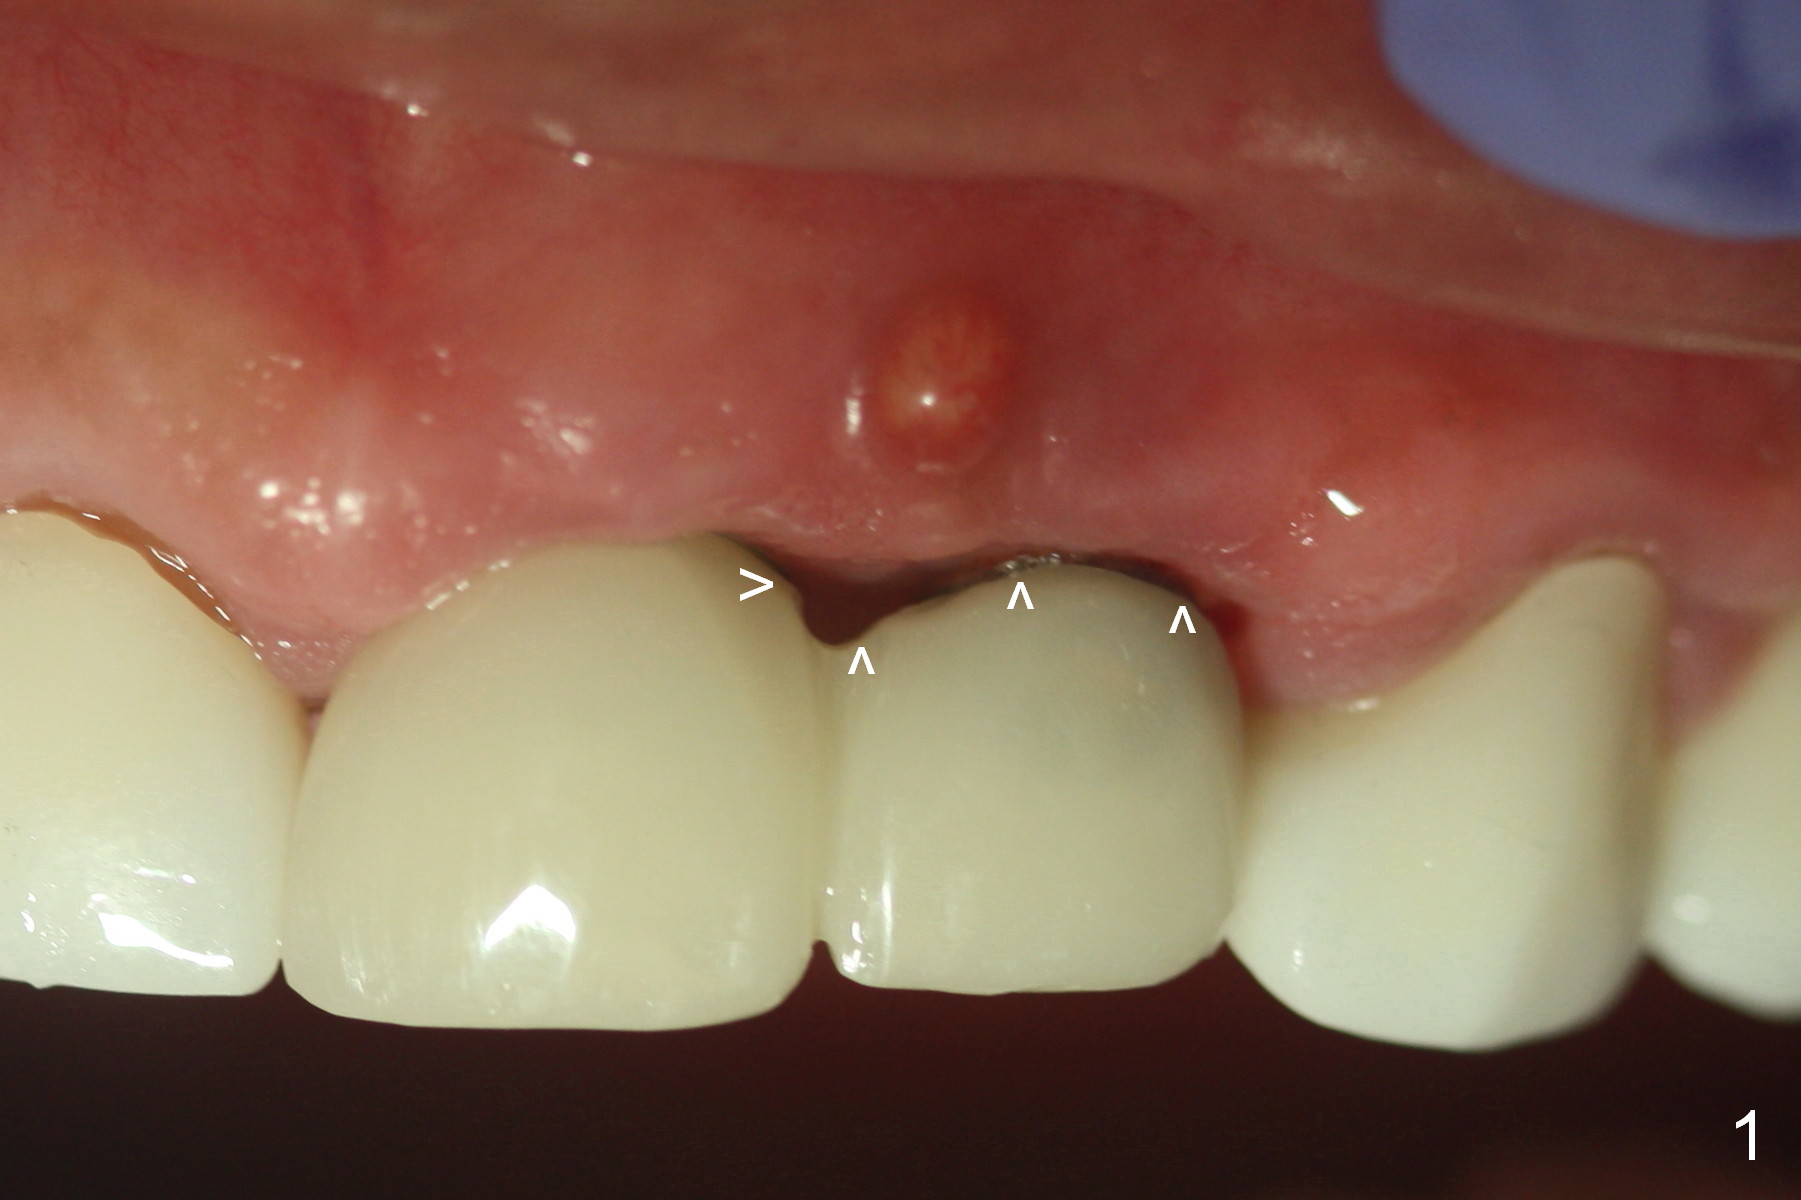

Close Gingival Embrasure (Gap)

Either with white or pink porcelain (Fig.1 arrowheads).